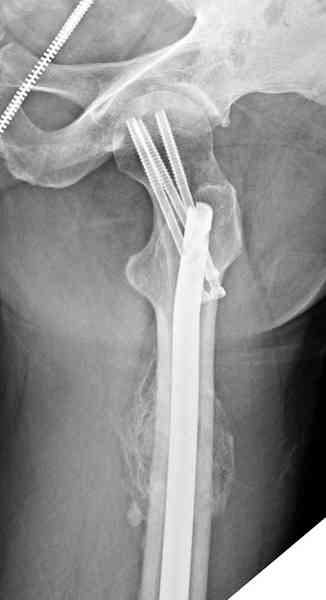

Здесь представлены снимки больного 65 лет, поступившего с диагнозом перелом

бедра после автоаварии.

В первый же день произведено антеградное штифтованием DePuy Trochanteric Nail.

На второй день (7) обнаружен пропущенный перелом,

и проведены шурурпы через и спереди штифта без удаления.

Послеоперационные снимки